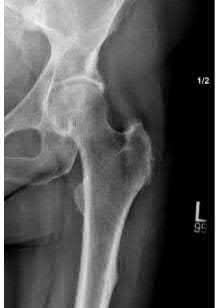

A 12-year-old obese boy presents with vague left thigh and knee pain. He is diagnosed with a Slipped Capital Femoral Epiphysis (SCFE) as seen in similar clinical scenarios.

During percutaneous in-situ fixation, unrecognized penetration of the guide wire into the hip joint occurs. What is the most likely specific complication resulting from this technical error?

Explanation

Chondrolysis is a severe complication of SCFE characterized by rapid destruction of the articular cartilage. While it can occur idiopathically, its most established iatrogenic cause is unrecognized intra-articular hardware penetration. The 'approach-withdraw' fluoroscopic technique is required during pinning to assure pins are entirely intraosseous. Avascular necrosis (AVN) is usually due to damage to the epiphyseal blood supply (retinacular vessels) secondary to the initial displacement, forceful closed reduction, or posterosuperior pin placement.